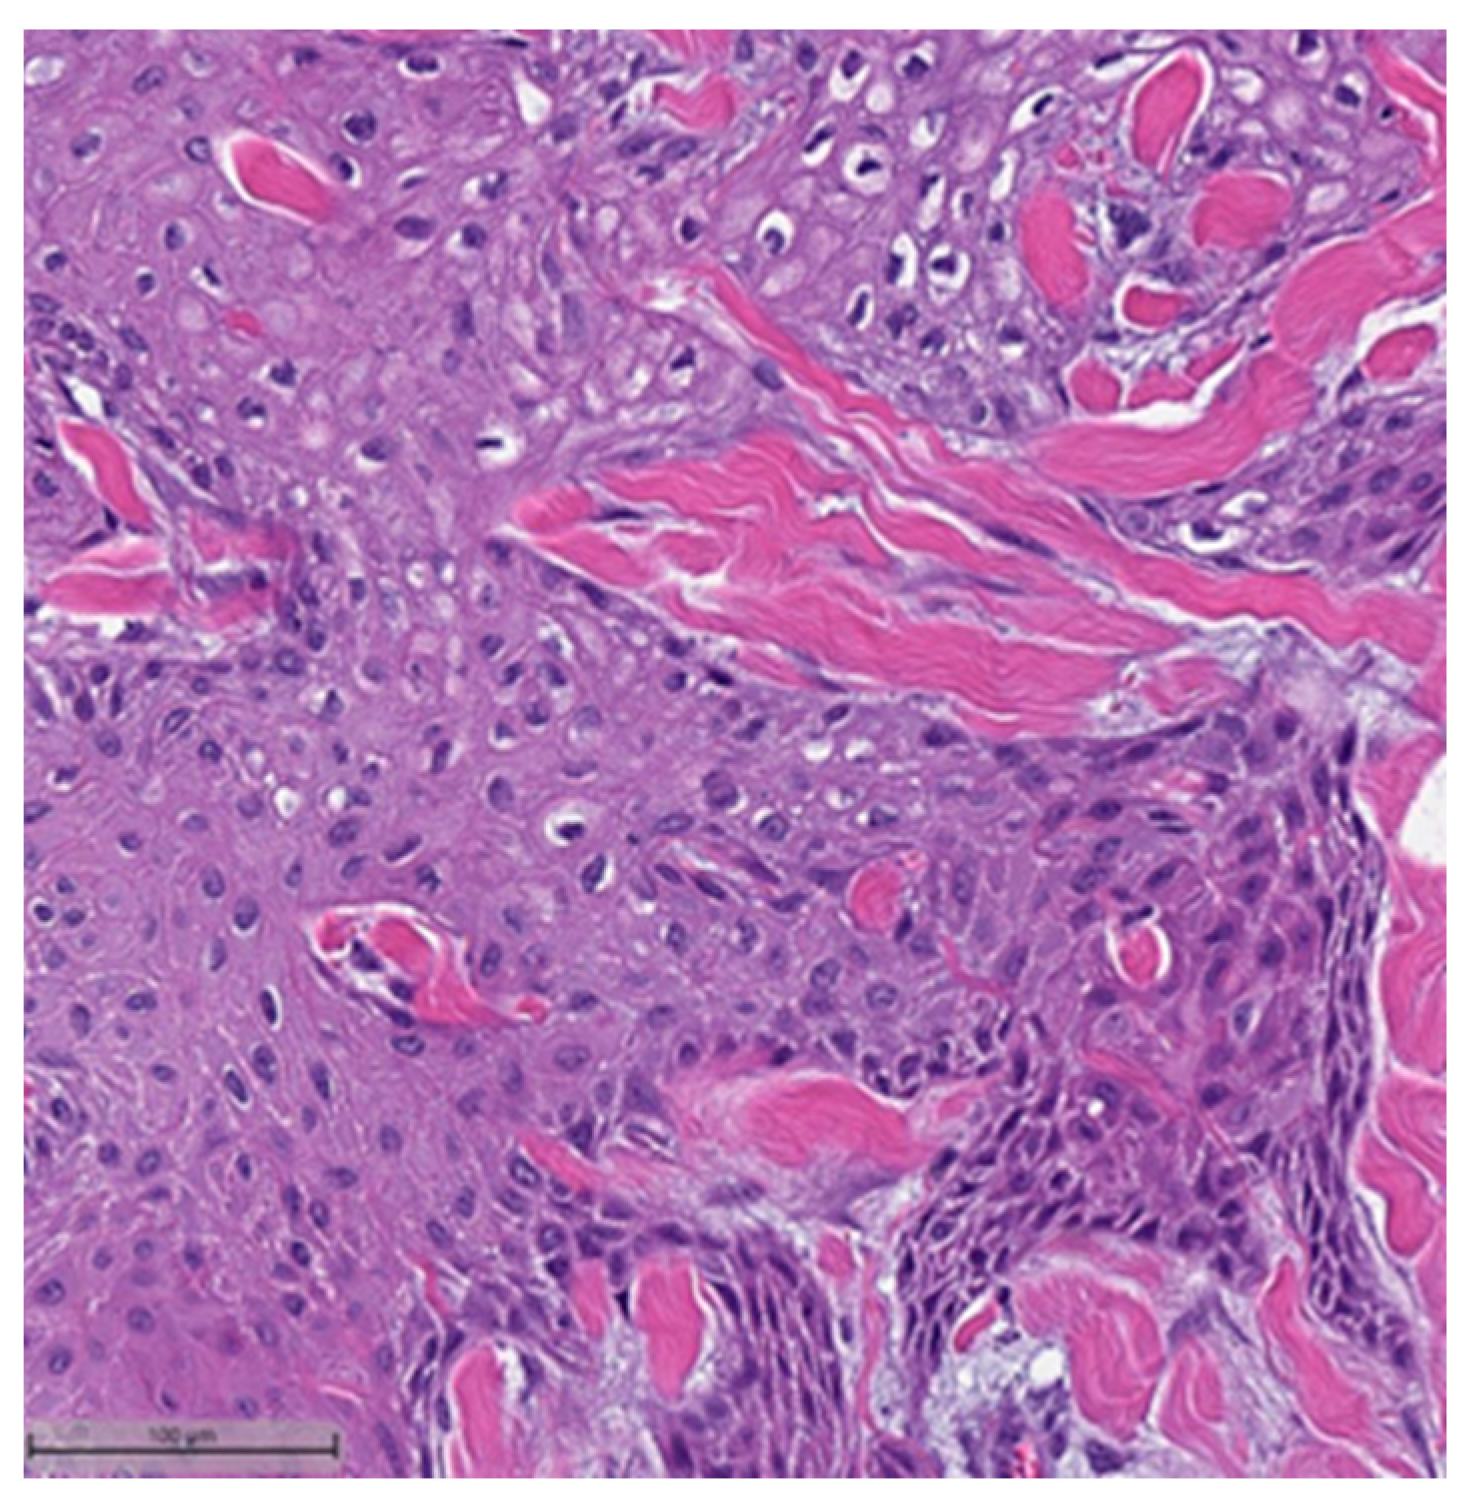

Figure 5.

Metaplastic breast carcinoma with chondroid differentiation (H&E, 20×).